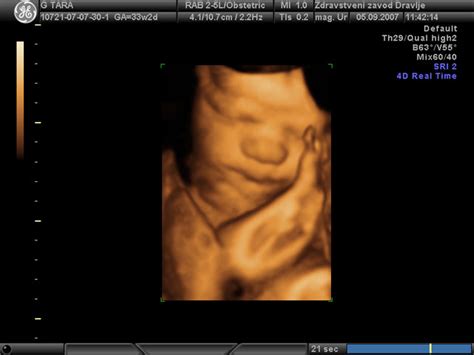

Morfologija ploda, ki se običajno opravi med 20. in 22. tednom nosečnosti, je ključni ultrazvočni pregled, ki ponuja poglobljen vpogled v razvoj otroka. To je eden najnatančnejših pregledov v celotni nosečnosti, med katerim ginekolog skrbno pregleda otroka od glave do pet. Med pregledom se merijo ključni parametri, kot so obseg glavice in trebuščka, dolžina stegnenice ter drugi deli telesa, da se zagotovi, da je otrokov razvoj skladen z gestacijsko starostjo. Preveri se delovanje srčka, razvoj vseh organov in sistemov, vključno s srcem, možgani, ledvicami in prebavnim sistemom. Posebna pozornost se posveča tudi morebitnim mehkim označevalcem, ki bi lahko nakazovali na kromosomske nepravilnosti.

Poleg osnovnih meritev se preverjajo tudi pretoki krvi v popkovnici in žilah, kar zagotavlja, da otrok prejema dovolj kisika in hranil. Položaj posteljice in količina plodovnice sta prav tako pomembna dejavnika, ki ju oceni ultrazvok. Morfologija je tudi priložnost, da starši izvejo spol otroka, če si tega želijo. Izkušnja, ko je bil mini ocenjen kot nekoliko manjši, kar je bila stalnica čez celo nosečnost, pa je poudarila pomen teh meritev za spremljanje rasti otroka. Kljub temu, da je bil otrok ocenjen kot manjši, je bil izgled, da je vse v najlepšem redu, vir velikega olajšanja pred načrtovanim "babymoonom".